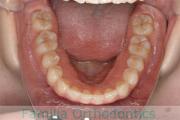

No.20V-499

- 主な症状:

- 上顎前突

- その他の症状:

- 叢生

- 年齢:

- 16歳

- 性別:

- 女性

- 抜歯部位

- 上:

- 44

- 下:

- 8558

- 主な使用装置:

- FEA

- 治療にかかった費用:

- 85万円

上の前歯が出っ歯気味なのを治したいということで来院されました。上下左右から小臼歯を抜歯して、歯科矯正用アンカースクリューを併用したマルチブラケット法により治療を行いました。動きの悪い歯やコントロールに苦労した場面があり、4年強・50回程度の通院が必要でした。

下顎前歯の叢生(でこぼこ、凹凸、ガタガタ)が著しく、後戻りのリスクが高い部位となります。